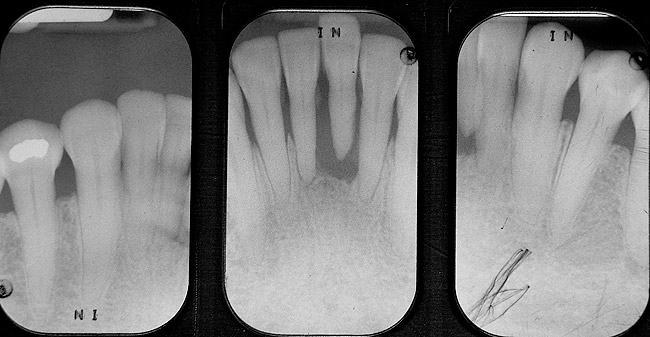

Figure 5a  Radiograph of severe periodontal bone loss on the mandibular left central incisor.

Figure 5a

Figure 5b  Facial view of the periodontally compromised central incisor.

Figure 5b

Figure 5c  Facial view after extraction of the central incisor.

Figure 5c

Figure 5d  Extracted mandibular left central incisor.

Figure 5d

Figure 5e  Natural tooth pontic after filling in root canal space, shaping the root surface to be the pontic, and placing the lingual channel in the tooth crown.

Figure 5e

Figure 5f  Lingual view of fiber-reinforced (Ribbond THM) splint-bridge at 6 months.

Figure 5f

Figure 5g  Facial view of fiber-reinforced splint-bridge at 6 months.

Figure 5g

Fiber-reinforced composite resins also can be used to fabricate direct-placement FPDs. Both UHMWPE and glass fibers can be used for direct-placement fiber-reinforced restorations (Table 2). In cases of the replacement of a single anterior tooth resulting from trauma, severe periodontal disease, or for endodontic reasons, the patient often finds this event to be catastrophic and there is urgency for the tooth to be replaced in a single visit. For these clinical situations, direct-placement pontics fabricated from composite resin, a denture tooth, or using the patient’s natural tooth with fiber reinforcement has been reported (Figure 5A through Figure 5G).52,53 The same technique can be used as an interim fixed restoration during implant placement and restoration.54 In some cases, after orthodontic treatment of the patient with congenitally missing maxillary lateral incisors, a direct-placement, fiber-splint FPD can be used to restore the missing tooth and provide for fixed orthodontic retention. This is especially pertinent for the young patient (teenager) in whom a conventional FPD or an implant is not yet indicated or practical for the given clinical situation.55,56 In orthodontics, fiber-reinforced composite resins have also been described for use a directly placed space maintainer and for fixed orthodontic retention.57-60